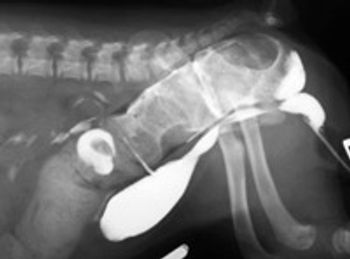

Atresia ani is a congenital embryological anomaly in which the hindgut fails to fully communicate with the perineum.